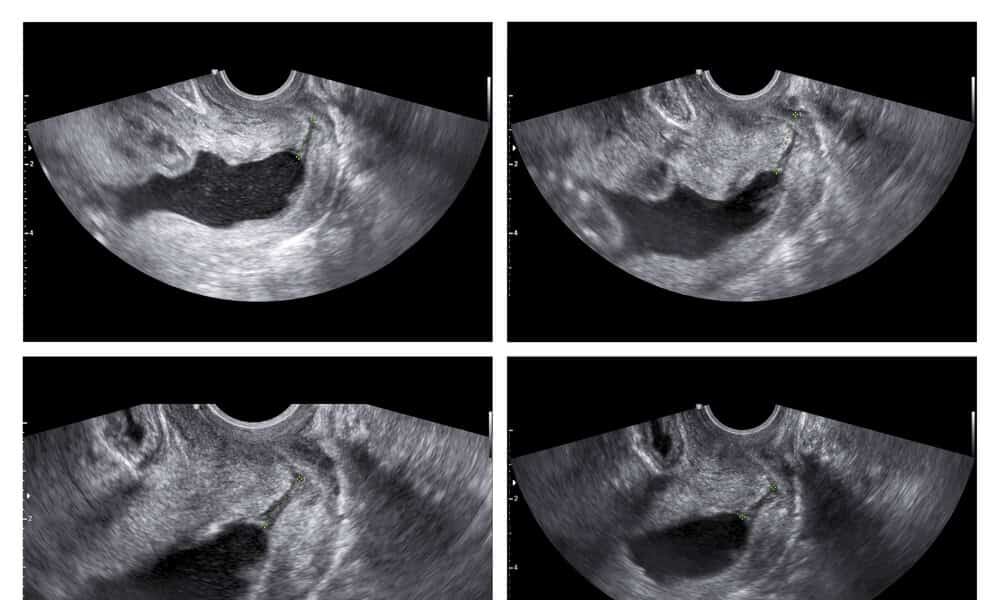

Η έρευνα διενεργήθηκε τη δεκαετία 2007-2017 σε περίπου 16.000 γυναίκες και αφορούσε στον πρώιμο έλεγχο των οργάνων του εμβρύου. Ενσωματώνοντας στο υπερηχογράφημα της αυχενικής διαφάνειας νέους υπερηχογραφικούς δείκτες, βρέθηκε ότι μπορούν να αυξηθούν σημαντικά τα ποσοστά διάγνωσης προβλημάτων της καρδιάς και της σπονδυλικής στήλης σε πρώιμο στάδιο της κύησης, δηλαδή περίπου στον τρίτο μήνα της εγκυμοσύνης.

Η έρευνα παρουσιάστηκε στο 17ο Παγκόσμιο Συνέδριο της Εμβρυομητικής Ιατρικής που έγινε στην Αθήνα, από την Μαιευτήρα-Γυναικολόγο, Δρ. Αθηνά Σούκα, Υπεύθυνη του Τμήματος Εμβρυομητρικής Ιατρικής του ΛΗΤΩ, η οποία -μεταξύ άλλων- τόνισε: «Οι νέοι υπερηχογραφικοί δείκτες – εξέταση της τριγλώχινας βαλβίδας, της καρδιάς και εξέταση του οπισθίου εγκεφάλου – μας βοήθησαν να διαγνώσουμε περίπου τις μισές σοβαρές καρδιακές ανωμαλίες και τα 2/3 των εμβρύων με σοβαρή βλάβη της σπονδυλικής στήλης, σε πρώιμο στάδιο της κύησης».